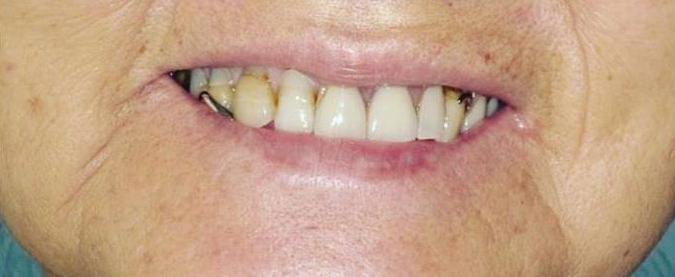

Can just four implants replace all of the teeth on the top or the bottom of your mouth? Thanks to advances in dental implant technology, that answer is a resounding yes.

Tooth loss is extremely common among adults, especially as we age. Rather than living with the discomfort and hassles of dentures, many people are opting for what is called “all-onfour” dental implant restoration.

An implant is a small titanium screw

that fits inside your jawbone and replaces the root-part of a missing tooth. Minor surgery is required to insert the implants. Once the implant is in place, a crown is attached to give you a highly realisticlooking and functional prosthetic tooth.

You do not need a dental implant for each and every one of your missing teeth. All you need is four precisely placed implants on the top of your mouth, and four on the bottom, to restore your full smile. That’s the beauty of the all-on-four. And because the implant is made of titanium, it has the unique ability to fuse to living bone and function as part of it. So eventually, the dental implant becomes part of the jawbone and serves as a strong, longlasting foundation for your new teeth.

Besides ensuring that your implants are permanently fixed in place, this bone fusion has another important benefit: it prevents future bone loss in the jaw. This helps to maintain a more youthful facial structure – and better oral health. But perhaps the biggest

Please see “All-On-Four,” page 61